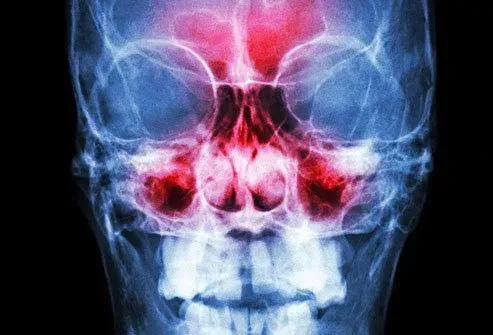

Вашите синуси са подути

Една проста настинка може да разпали кухите зони зад скулите и челото ви. Подуването може да причини болка там, която се влошава, когато се наведете. Може да е трудно да дишате, защото слузът, който може да стане дебел и жълт или зелен, не се оттича правилно. Лекарствата без рецепта често могат да ви помогнат да го управлявате. Няма нужда да се обаждате на Вашия лекар, освен ако симптомите не са лоши, не изчезвайте или не се влошават.